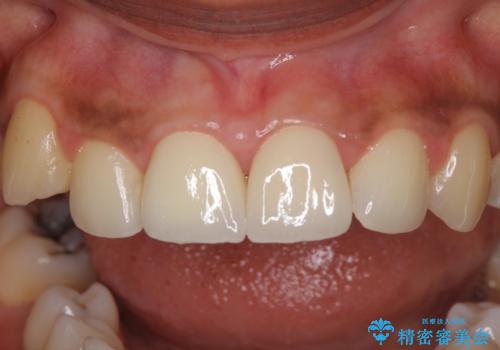

- 上の前歯2本の審美障害を気にして来院された患者様です。樹脂が無造作に充填されており、色合いも形態も不自然で、歯肉も腫れているため、オールセラミッククラウンにて補綴することとしました。

充填されたレジンを取り除いたところ、歯肉の炎症による出血が認められました。セラミッククラウン装着後は歯肉が腫れることもなく、仕上がりも自然な歯のようになり、患者様には大変満足していただきました。